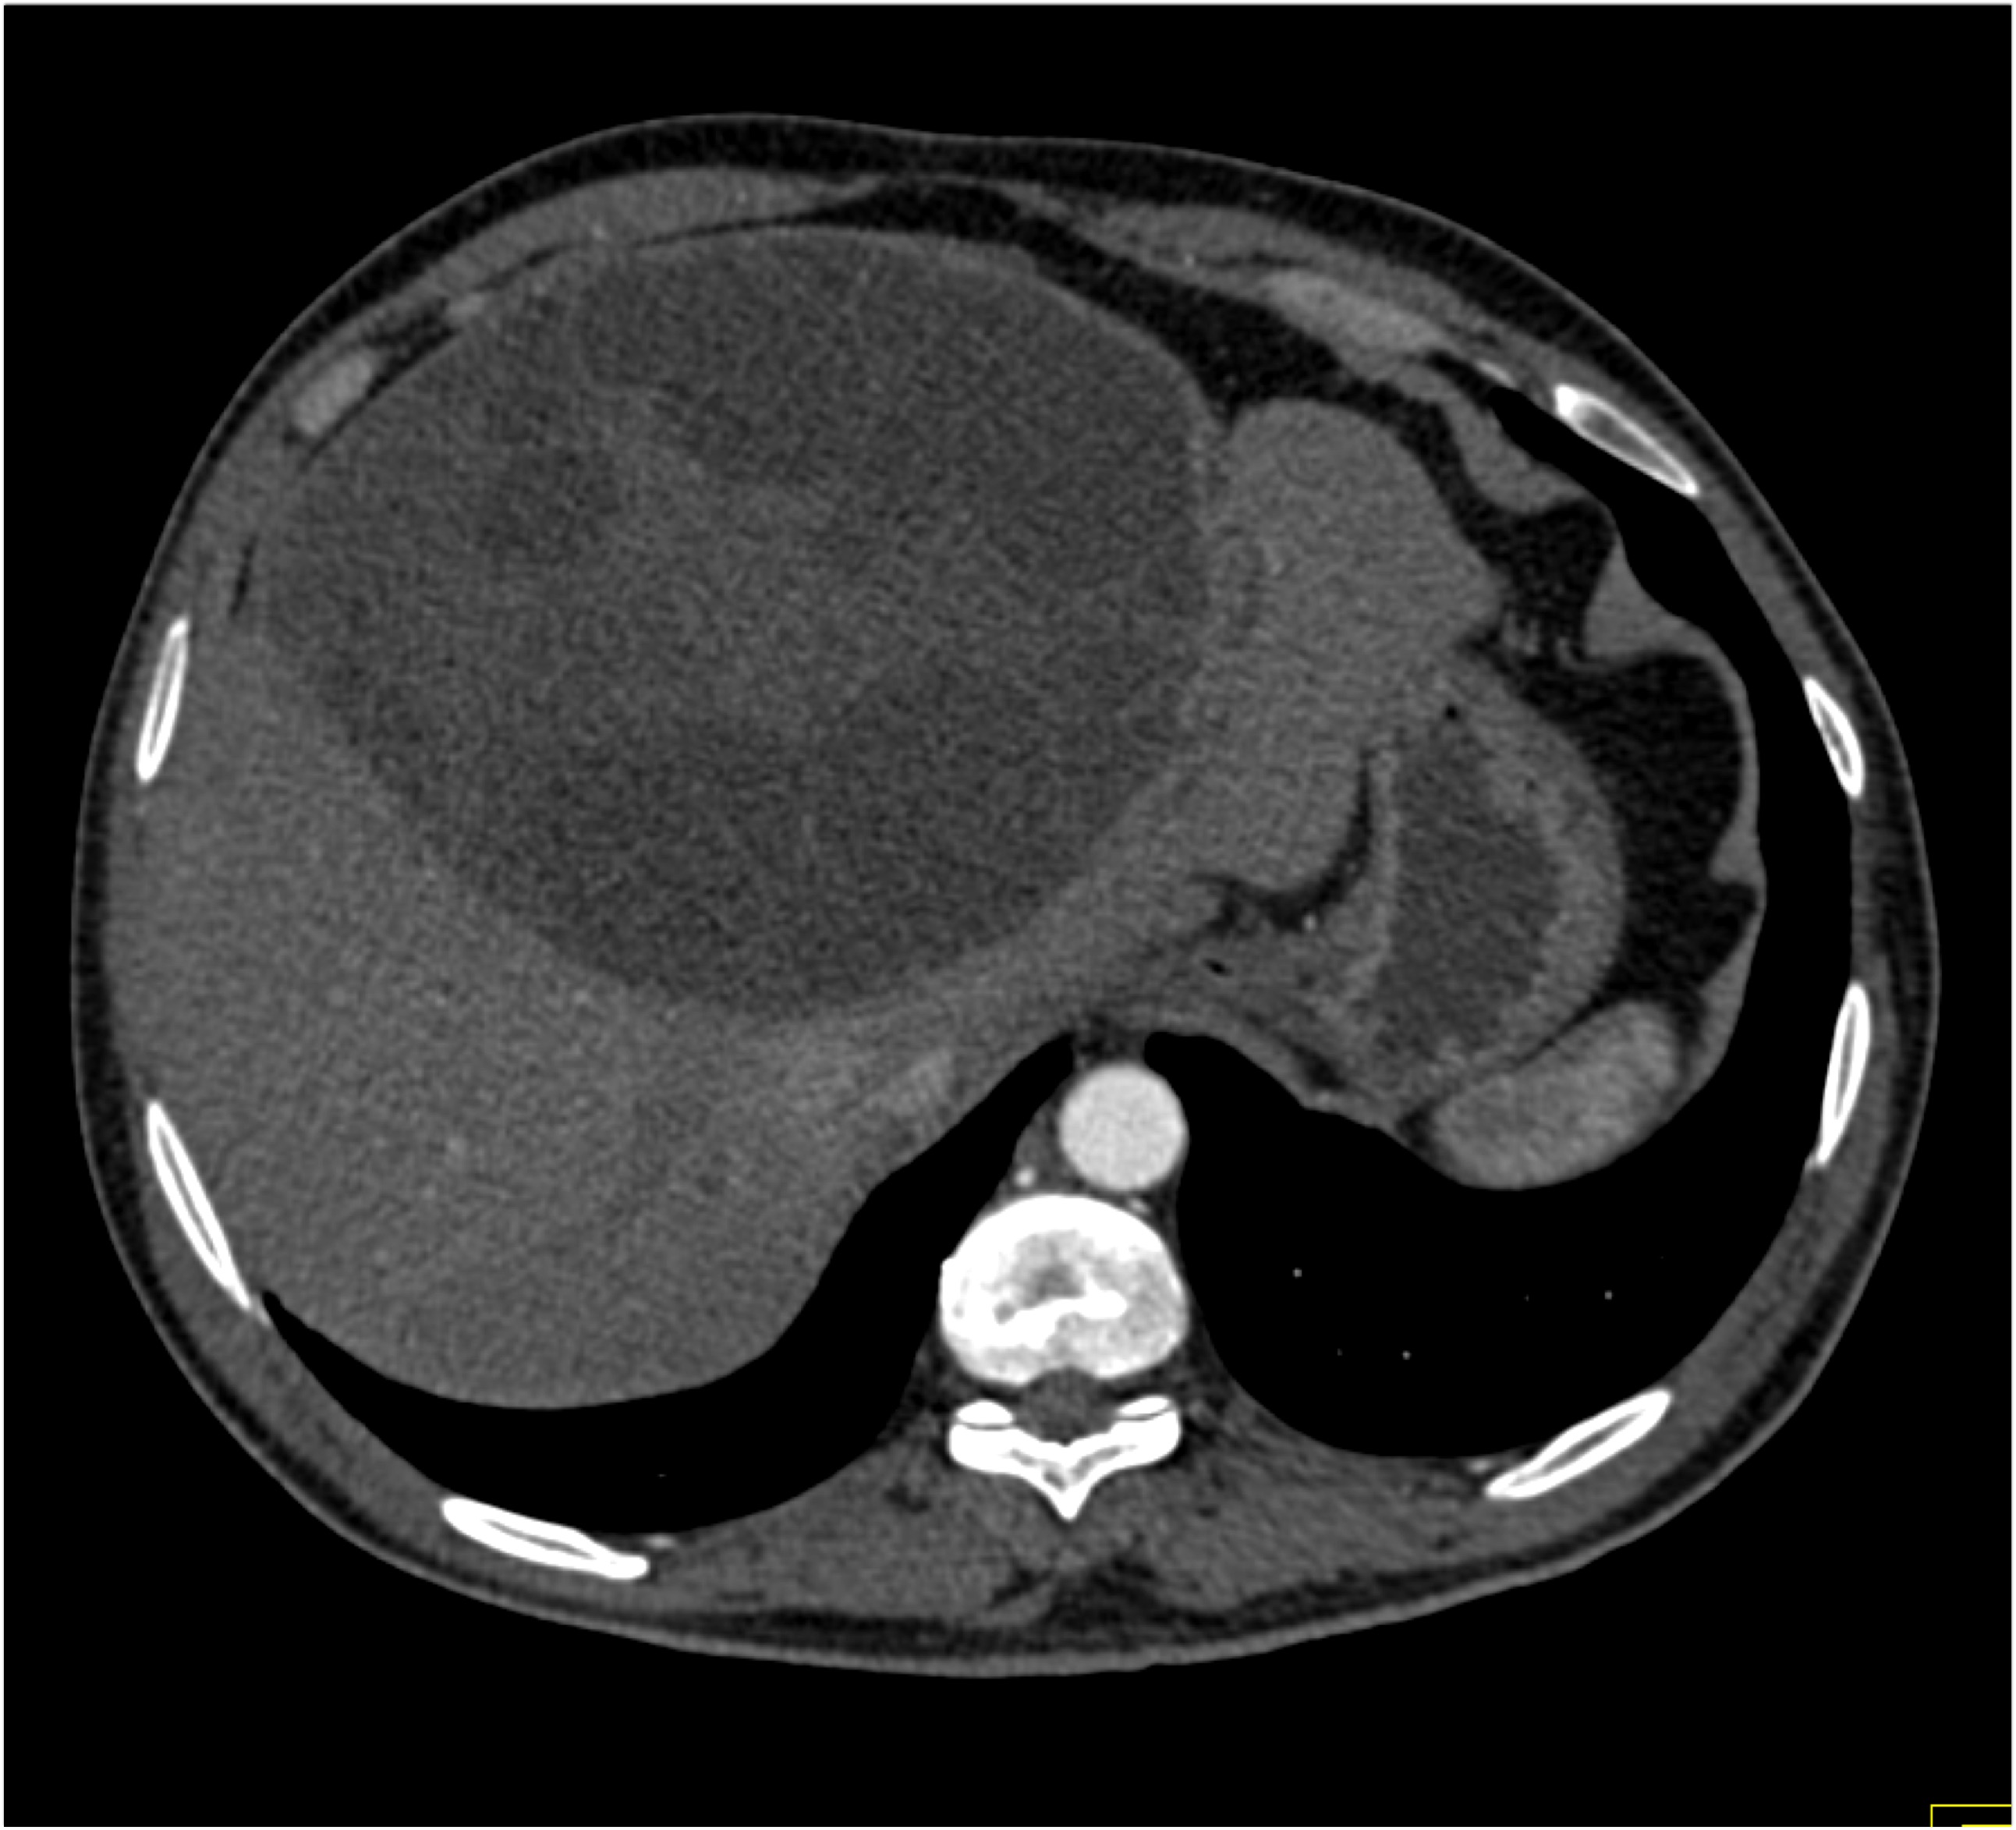

1) The most likely diagnosis in this patient with LUQ pain is?

adrenal myelolipoma

adrenal ganglioneuroma

adrenal adenoma

pheochromocytoma